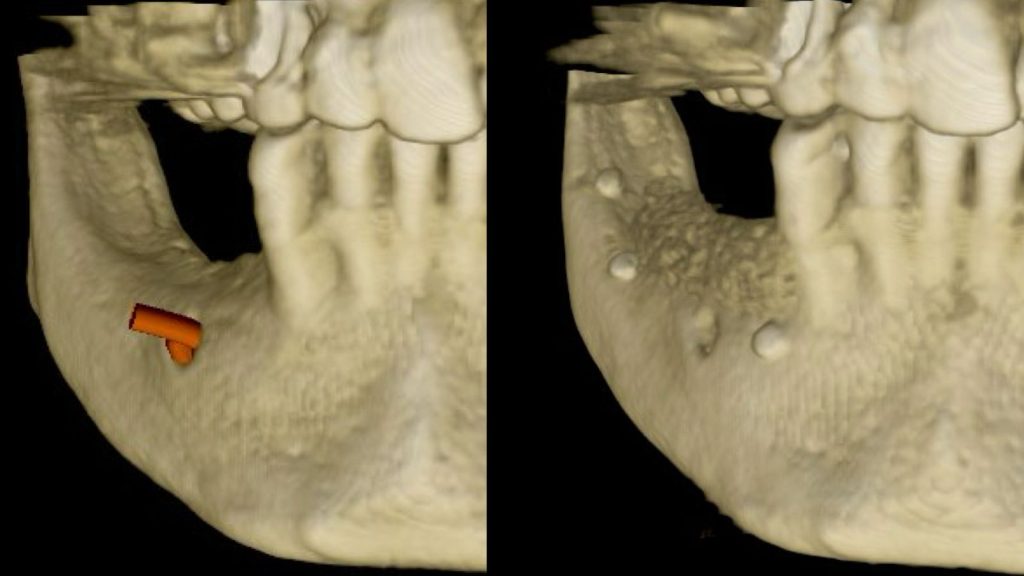

- Lecture clinique et radiologique (panoramique, CBCT : bases de lecture)

- Identifier un déficit osseux nécessitant une ROG